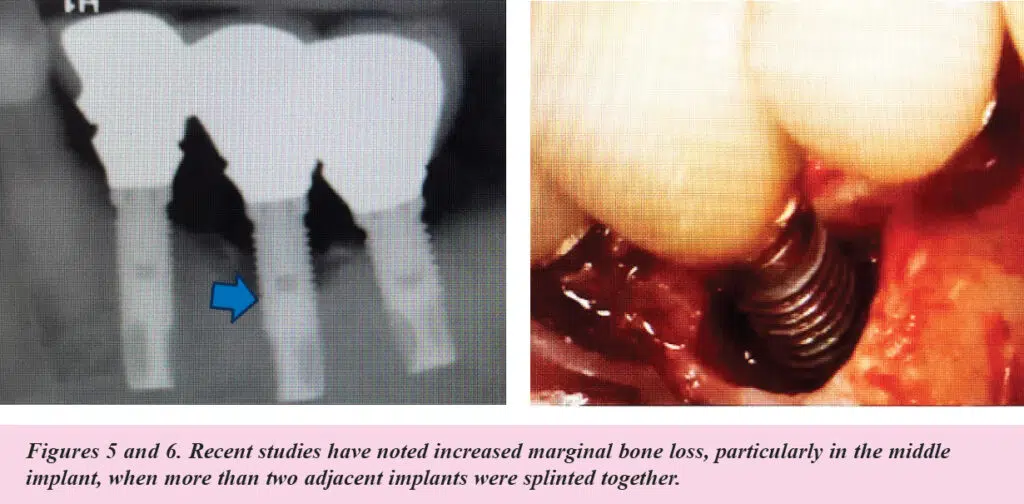

According to the Report, splinted vs nonsplinted restorations also factor into the risk for peri-implantitis and marginal bone loss.

Splinted restorations offer better stability in full-arch restorations, but potentially increase the risk of biofilm buildup if not designed with adequate spacing to facilitate oral hygiene efforts.

Recent studies cited by the AAP/AO also noted increased marginal bone loss, particularly in the middle implant, when three adjacent implants were splinted together. (See Figures 5 and 6.)